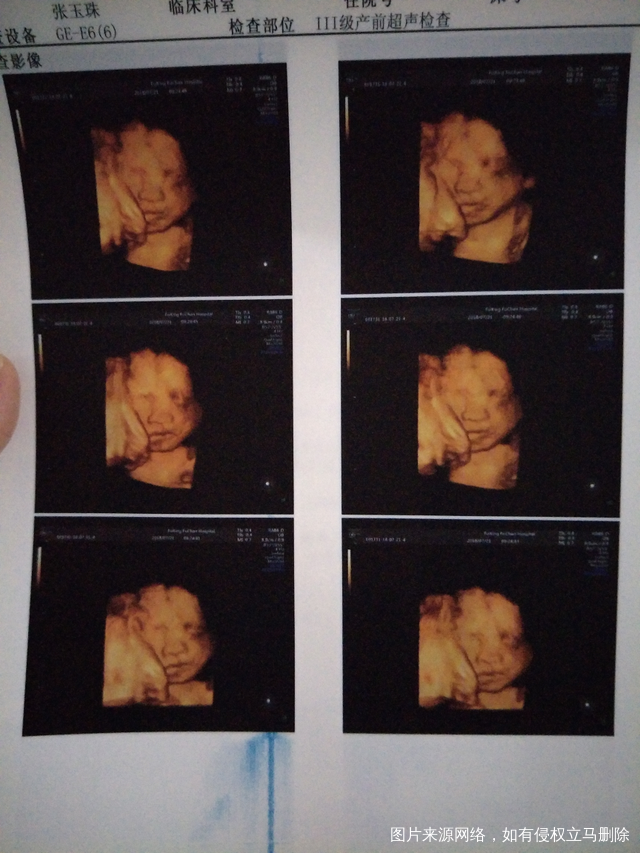

六个多月做的四维彩超宝宝右已经怎么有点青,正常吗?

帮忙看一下

求助医生